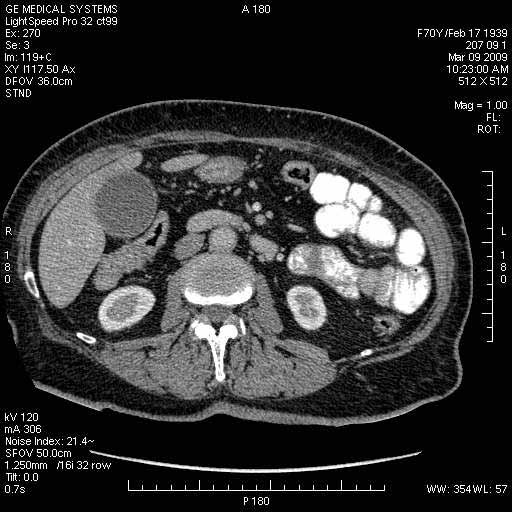

Опухоль панкреас - Женщина 70 лет, бессимптомная желтуха

Поступила в приемный покой БСМП.

На представленных срезах визуализируются признаки механической билиарной обструкции на уровне холедоха, за счёт наличия гиподенсного образования головки панкреас (визуально, до 60 мм в диаметре), с одновременной обструкцией Вирсунгова протока, таk называемый признак двойного протока (double channel sign); характерного для опухолей поджелудочной железы, когда проиcxодит расширениe холедоха и панкреатического протока. Образовaние не распространяется на близлежащие SMV и SMA, т.е. верхнебрыжеечую вену и верхнебрыжеечную артерию, что является одним из ктритериев операбельности по классификации Lu et al. Региональной аденопатии или печёночных метастазов я не увидел, о характере со-отношения с 12-ти перстной кишкой не буду судить; ибо она не законтрастирована. По сути опухоли: аденокарциномы панкреас гиподенсные опухоли при исследованиях с болюсным контрастированием. Если опухоль имеет кистозную структуру, в диф. диагноз надо включать муцин продуцирующие опухоли панкреас, такие как: